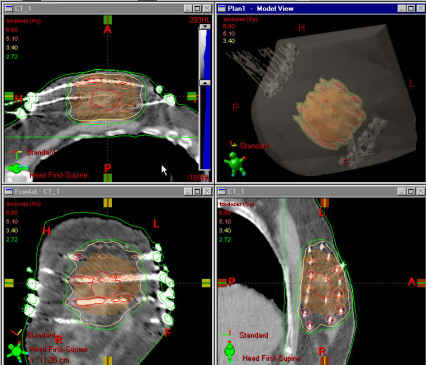

Photo: A radiation treatment plan for multi-catheter breast brachytherapy.

Breast brachytherapy is used for accelerated partial breast treatment. Traditional radiation therapy for breast cancer involves approximately six weeks of daily external treatments. Some women are candidates for partial breast treatment, which is a promising new treatment delivered over just five days. Several methods of partial breast treatment are available at Massey, including multi-catheter implants, both the Contura and MammoSite devices, and three-dimensional conformal external beam therapy.